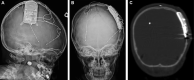

Results: Of 35 patients identified, 17 were <18 yr at the time of RNS implantation, including a 3-yr-old patient. Four patients (11%) had concurrent resection. Three complications, requiring additional surgical interventions, were noted in young adults (2 infections [6%] and 1 lead fracture [3%]). No complications were noted in children. Among the 32 patients with continued therapy, 2 (6%) achieved seizure freedom, 4 (13%) achieved ≥90% seizure reduction, 13 (41%) had ≥50% reduction, 8 (25%) had <50% reduction, and 5 (16%) experienced no improvement. The average follow-up duration was 1.7 yr (median 1.8 yr, range 0.3-4.8 yr). There was no statistically significant difference for seizure reduction and complications between children and young adults in our cohort or between our cohort and the adult literature.

Conclusion: These preliminary data suggest that RNS is well tolerated and an effective off-label surgical treatment of drug-resistant epilepsy in carefully selected pediatric patients as young as 3 yr of age. Data regarding long-term efficacy and safety in children will be critical to optimize patient selection.